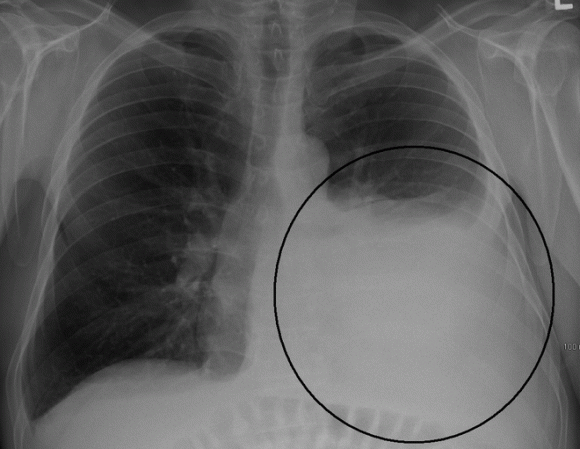

– Khi chụp X-quang phổi thấy hình mờ đậm, đồng đều, dịch thường ở dưới thấp, có khi mờ ở cả hai bên phổi, tim bị đẩy sang bên đối diện.